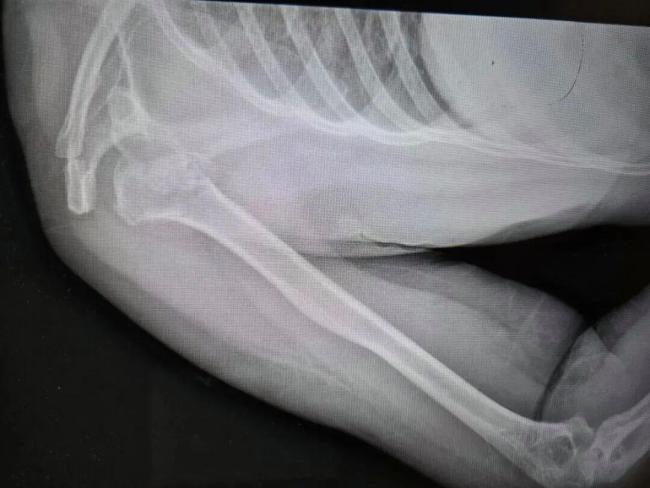

近日,河南50岁的张大姐在睡梦中粉碎性骨折,肩膀骨头碎成七八块,而她全程都在床上躺着。河南省人民医院创伤骨科主任刘涛对此表示难以置信,通常只有高空坠落或车祸撞击才会造成如此严重的骨折。像张大姐这样因癫痫导致的粉碎性骨折在临床及文献中极为罕见。

诊疗小组为张大姐制定了详细的治疗方案,将劈裂的肱骨骨头、后脱位等四大部分以及七八块碎裂的骨头都按原貌实现完整复位,并修复受损的肌腱,填充塌陷部分的支撑骨。目前,张大姐正在进一步接受癫痫相关管理和规范治疗。

原来,在最近3年里,张大姐经常出现突然的头晕和头疼症状,每次持续一两分钟后就恢复正常。她一直以为是劳累或是小毛病,从未在意。神经内科团队通过脑电图监测发现,张大姐在夜间癫痫发作时,大脑异常放电导致全身肌肉产生猛烈、极端的收缩。这种瞬间的力量通过杠杆作用,竟生生将她的骨头“震”碎并挤出了关节窝。